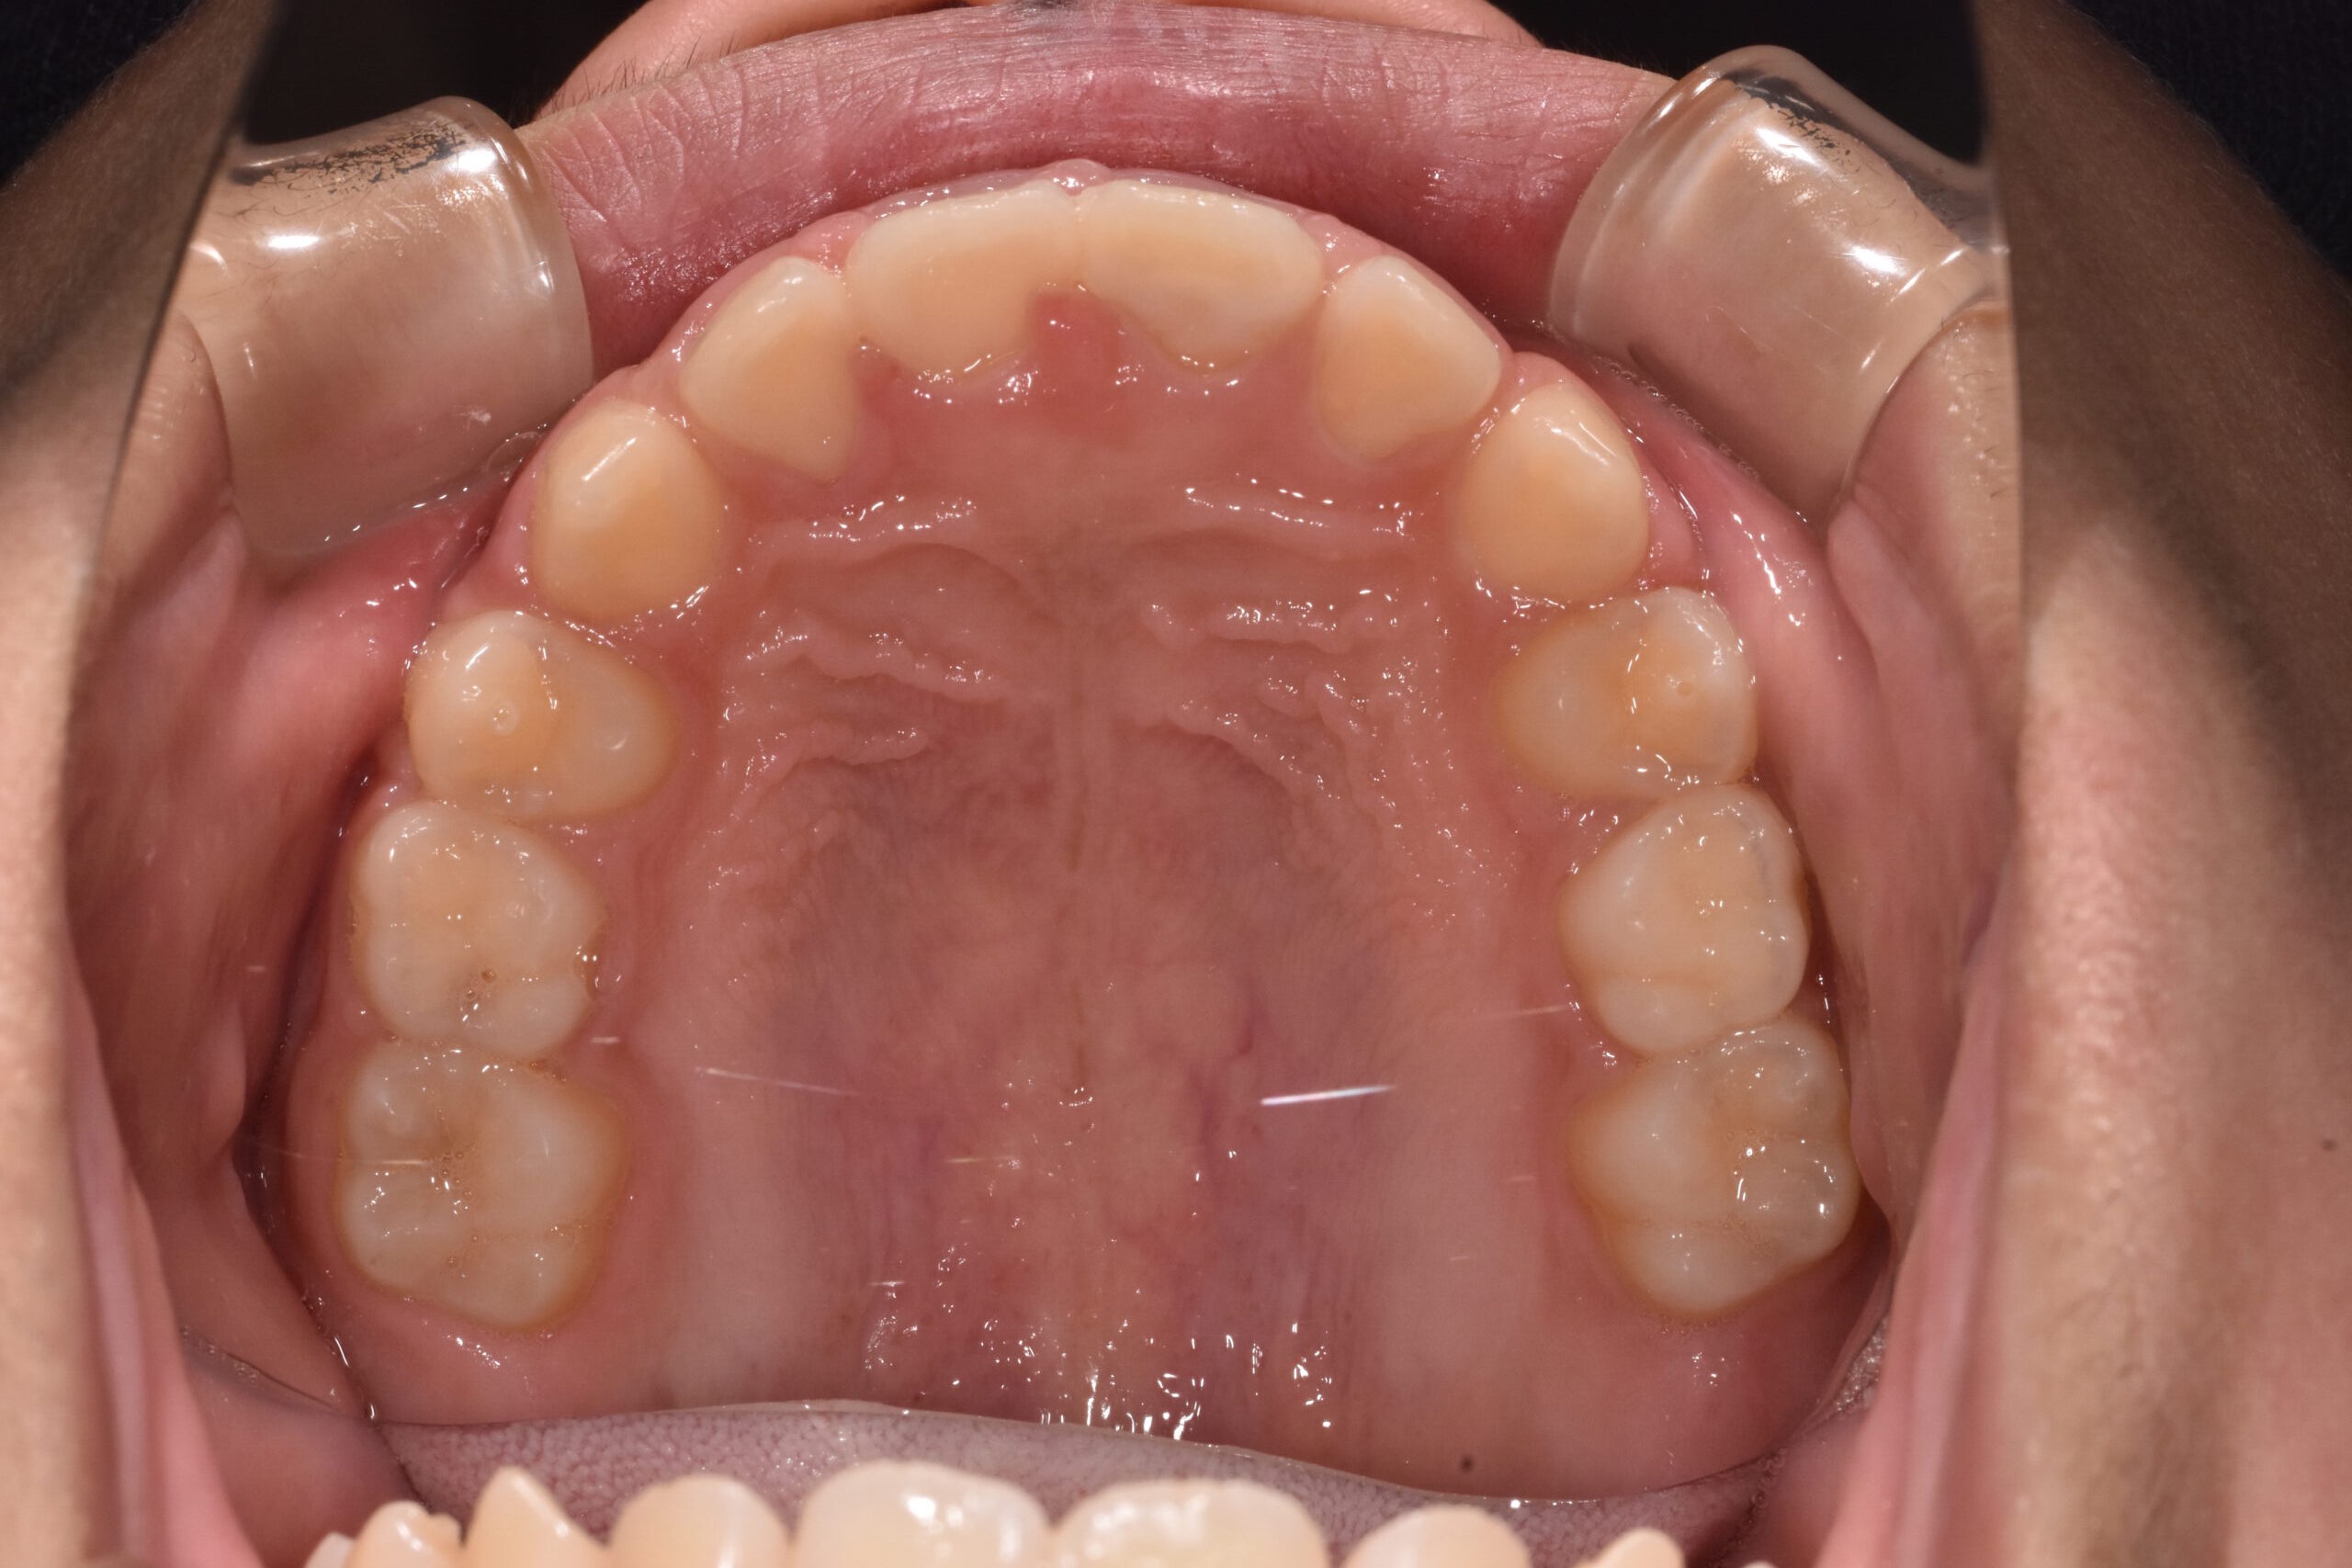

治療後

成長を利用した1期治療にて、マウスピース型装置や矯正装置を用い、歯並びと口元のバランスの改善を行いました

1年5ヶ月

15回

約48万円

治療のポイント:

・成長期を活かし、口元の突出感を改善

・歯並びだけでなく、横顔(Eライン)にも配慮

・将来的な抜歯や本格矯正の負担軽減を目指した治療

・必要に応じて2期治療へ移行できるよう設計